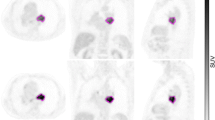

Image analysis (calculation of SAM)

A volume of interest (VOI1) was drawn using PMOD software over the primary tumour lesions of patients of substudy 1 on all reconstructed image sets (1- to 10-min reconstructed images) as well as over all individual metastatic liver lesions of patients of substudy 2 (scan 1 and scan 2). A second VOI (VOI2) was delineated around VOI1 directed to a small zone of homogeneous background. The borders of VOI1 were set at a reasonable distance from the tumour lesions in order to avoid PVE and to ensure that no spillover from the tumour lesion to VOI2 occurred (see Fig. 1). SAM and normalized SAM values were derived using the formulas described in the phantom study, but without the volume correction for VOI1, as this does not apply on patients. In patients with multiple liver metastases (substudy 2) SAM was calculated as the sum of the individual SAMs of the lesions.

18F-FDG PET scan of a patient with colorectal carcinoma metastasized to the liver. A volume of interest (VOI1, blue VOI) was set at a reasonable distance from the metastatic lesion in order to avoid PVE. A second VOI (VOI2, green VOI) was delineated around VOI1. Subtracting the background activity in VOI2-VOI1 from VOI1 yields SAM